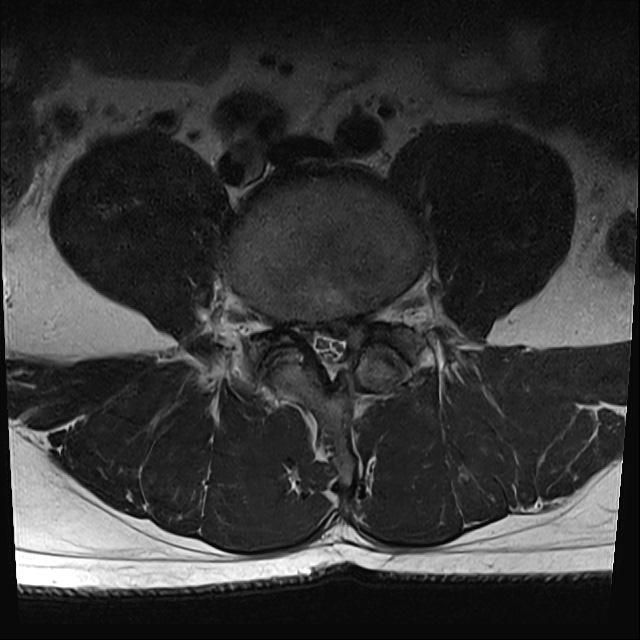

L4-5번 후궁절제술 경험이 있습니다. 근전도 검사에서 신경근병증 받았구요..재발인거 같아 수술고려중인데 판독부탁드립니다.감사합니다;).

• 2번 째 사진